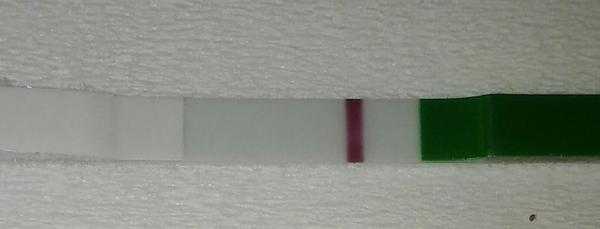

Ahojte baby potrebujem radu dnes som 9-10dpo, od včera mi je zle na žalúdku, vracala som, aj dnes mi je tak isto, tak je mi cudne... A test som si spravila až teraz poobede a nič tam špeciálne nevidím vy áno? Viem ze je to skoro, ale nedalo mi tak som si test spravila a zatiaľ tam nič nie je iba taky ako duch alebo len kanálik 🤔 neviem ťažko povedať..

@tinadeville no tebe to vidno pekne, ja som to mala takto isto voľným okom to lepšie bolo vidno